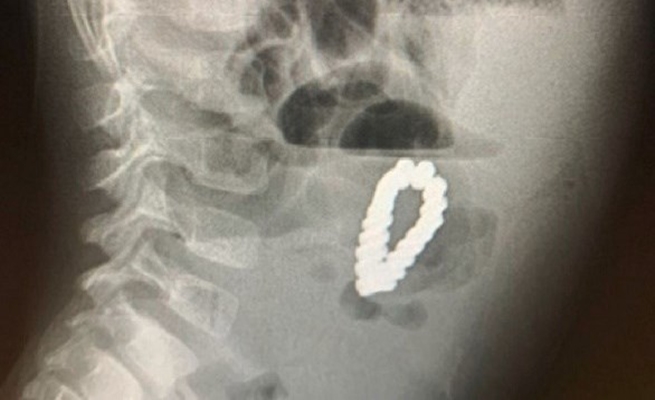

بدأت تفاصيل الواقعة عندما وصل الطفل إلى قسم الطوارئ وهو يعاني من آلام واضحة في البطن مع أعراض مرتبطة بعسر الهضم، وهو ما دفع الأطباء إلى إجراء فحوصات عاجلة للتأكد من عدم وجود انسداد أو ابتلاع أجسام غريبة. الأشعة التي تم إجراؤها أظهرت مفاجأة صادمة؛ سلسلة من المغناطيسات المعدنية موزعة بين المعدة والأمعاء الدقيقة بشكل متشابك.

بعد التشخيص، قرر الفريق الطبي اعتماد خيار المنظار العلوي للجهاز الهضمي بدلاً من الجراحة المفتوحة، وهي خطوة تتطلب مهارة عالية نظرًا لحجم وعدد وطبيعة الأجسام المعدنية داخل الجهاز الهضمي. وقد استغرقت العملية حوالي ساعة واحدة، تمكن خلالها الأطباء من إزالة المغناطيسات جميعها دون أي تمزق أو نزيف داخلي ودون الحاجة لفتح البطن.

تم استخراج 49 مغناطيسًا من المعدة والأمعاء الدقيقة.